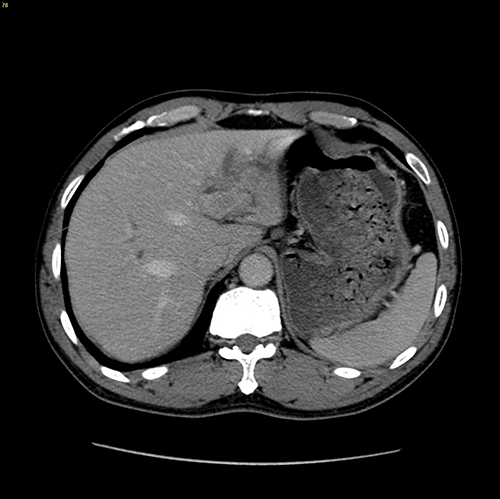

左肝管结石--左肝叶切除